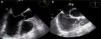

Em 2005, foi‐lhe implantado um cardioversor desfibrilhador (CDI) por taquicardia ventricular sincopal (Figura 1).

Realizou ETT/ETE, tendo sido modificado o diagnóstico da cardiopatia congénita de base para «transposição dos grandes vasos congenitamente corrigida» (TGVCC) e CIA baixa (conforme figuras). Foi feita a extração do sistema de CDI. Por se ter observado durante o seu seguimento em consultas de CDI, prévias ao internamento, períodos de bloqueio auriculoventricular de terceiro grau e grande dependência de pacing ventricular e por se querer que o doente fique com o mínimo de material protésico intravascular, colocou‐se pacemaker dupla‐câmara epicárdico e CDI subcutâneo. Teve alta clinicamente estável.